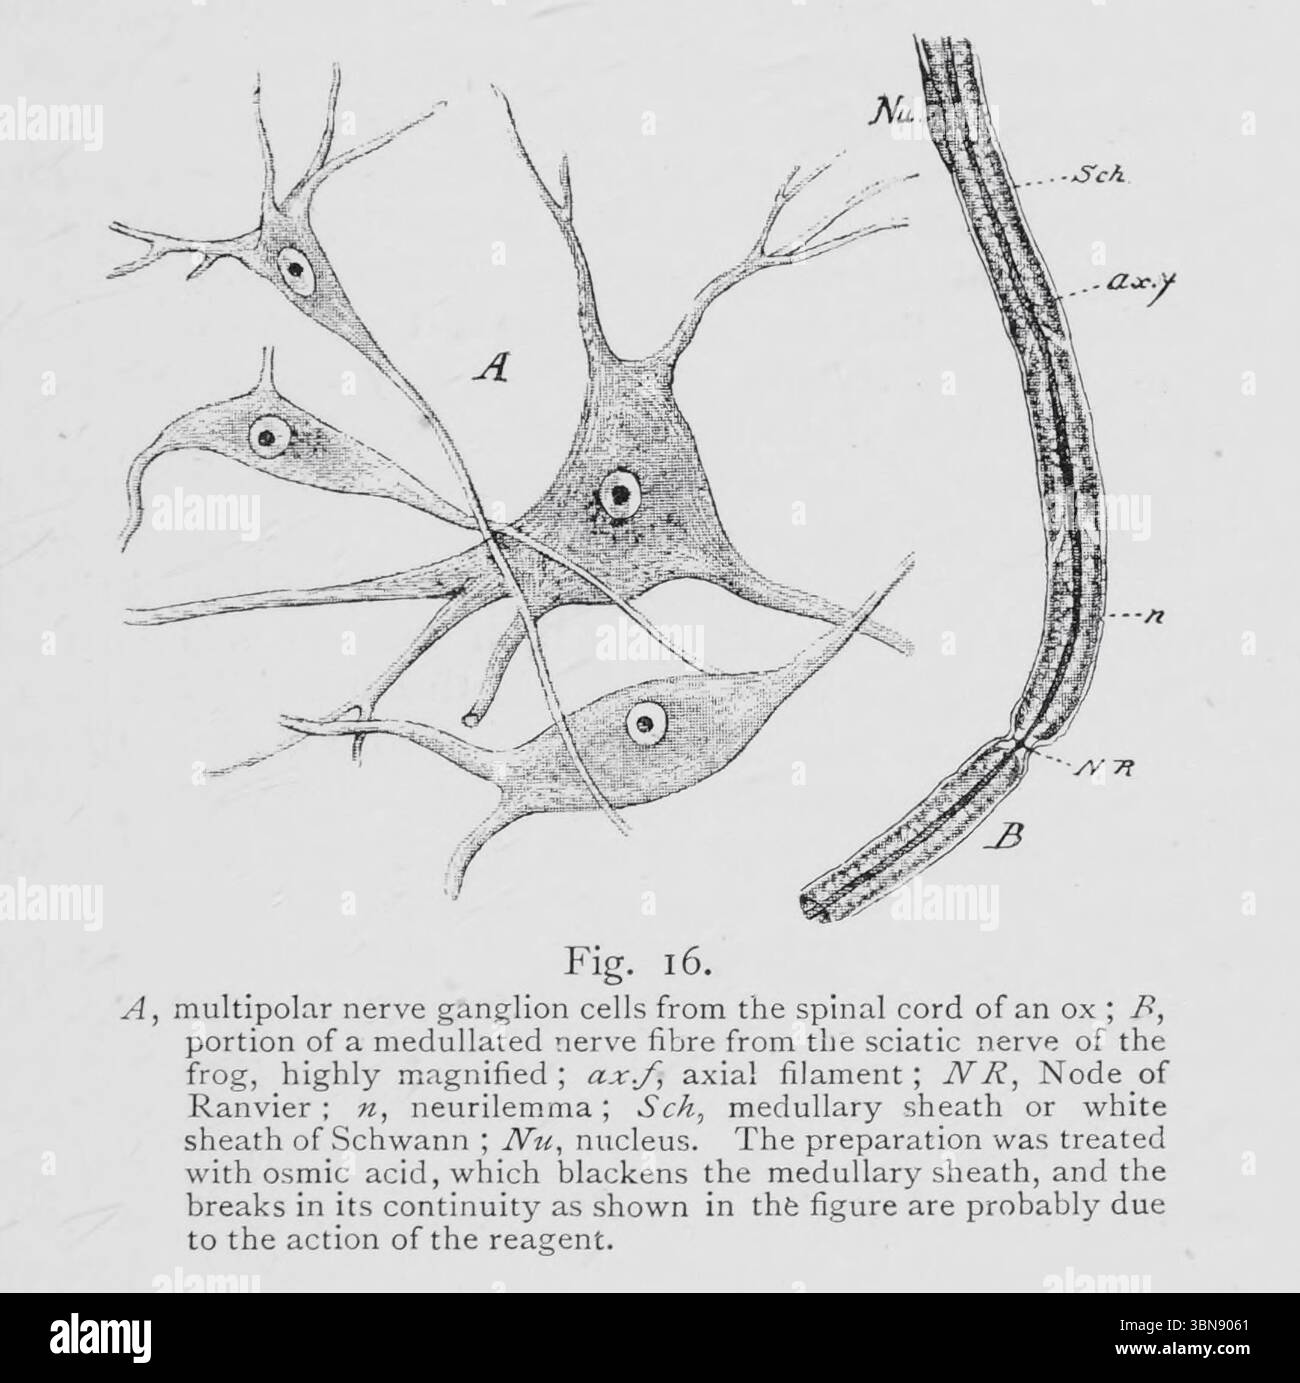

Cellules ganglionnaires nerveuses et fibre nerveuse A, cellules ganglionnaires nerveuses multipolaires de la moelle épinière d'un boeuf ; F, partie d'une fibre nerveuse médullée du nerf sciatique de grenouille, fortement agrandie ; Ax.f, filament axial ; JVR, nœud de Ranvier ; n, neurilemme ; SCK, gaine médullaire ou gaine blanche de Schwann ; JVu, noyau. La préparation a été traitée avec de l'acide osmique, qui noircit la gaine médullaire, et les ruptures de sa continuité telles que représentées sur la figure ci-dessus sont probablement dues à l'action du réactif. De l'ouvrage ' une introduction à l'étude de l'anatomie comparée des animaux ' de Bo Banque D'Imageshttps://www.alamyimages.fr/image-license-details/?v=1https://www.alamyimages.fr/cellules-ganglionnaires-nerveuses-et-fibre-nerveuse-a-cellules-ganglionnaires-nerveuses-multipolaires-de-la-moelle-epiniere-d-un-boeuf-f-partie-d-une-fibre-nerveuse-medullee-du-nerf-sciatique-de-grenouille-fortement-agrandie-ax-f-filament-axial-jvr-noeud-de-ranvier-n-neurilemme-sck-gaine-medullaire-ou-gaine-blanche-de-schwann-jvu-noyau-la-preparation-a-ete-traitee-avec-de-l-acide-osmique-qui-noircit-la-gaine-medullaire-et-les-ruptures-de-sa-continuite-telles-que-representees-sur-la-figure-ci-dessus-sont-probablement-dues-a-l-action-du-reactif-de-l-ouvrage-une-introduction-a-l-etude-de-l-anatomie-comparee-des-animaux-de-bo-image684309865.html

Cellules ganglionnaires nerveuses et fibre nerveuse A, cellules ganglionnaires nerveuses multipolaires de la moelle épinière d'un boeuf ; F, partie d'une fibre nerveuse médullée du nerf sciatique de grenouille, fortement agrandie ; Ax.f, filament axial ; JVR, nœud de Ranvier ; n, neurilemme ; SCK, gaine médullaire ou gaine blanche de Schwann ; JVu, noyau. La préparation a été traitée avec de l'acide osmique, qui noircit la gaine médullaire, et les ruptures de sa continuité telles que représentées sur la figure ci-dessus sont probablement dues à l'action du réactif. De l'ouvrage ' une introduction à l'étude de l'anatomie comparée des animaux ' de Bo Banque D'Imageshttps://www.alamyimages.fr/image-license-details/?v=1https://www.alamyimages.fr/cellules-ganglionnaires-nerveuses-et-fibre-nerveuse-a-cellules-ganglionnaires-nerveuses-multipolaires-de-la-moelle-epiniere-d-un-boeuf-f-partie-d-une-fibre-nerveuse-medullee-du-nerf-sciatique-de-grenouille-fortement-agrandie-ax-f-filament-axial-jvr-noeud-de-ranvier-n-neurilemme-sck-gaine-medullaire-ou-gaine-blanche-de-schwann-jvu-noyau-la-preparation-a-ete-traitee-avec-de-l-acide-osmique-qui-noircit-la-gaine-medullaire-et-les-ruptures-de-sa-continuite-telles-que-representees-sur-la-figure-ci-dessus-sont-probablement-dues-a-l-action-du-reactif-de-l-ouvrage-une-introduction-a-l-etude-de-l-anatomie-comparee-des-animaux-de-bo-image684309865.htmlRM3BN9061–Cellules ganglionnaires nerveuses et fibre nerveuse A, cellules ganglionnaires nerveuses multipolaires de la moelle épinière d'un boeuf ; F, partie d'une fibre nerveuse médullée du nerf sciatique de grenouille, fortement agrandie ; Ax.f, filament axial ; JVR, nœud de Ranvier ; n, neurilemme ; SCK, gaine médullaire ou gaine blanche de Schwann ; JVu, noyau. La préparation a été traitée avec de l'acide osmique, qui noircit la gaine médullaire, et les ruptures de sa continuité telles que représentées sur la figure ci-dessus sont probablement dues à l'action du réactif. De l'ouvrage ' une introduction à l'étude de l'anatomie comparée des animaux ' de Bo